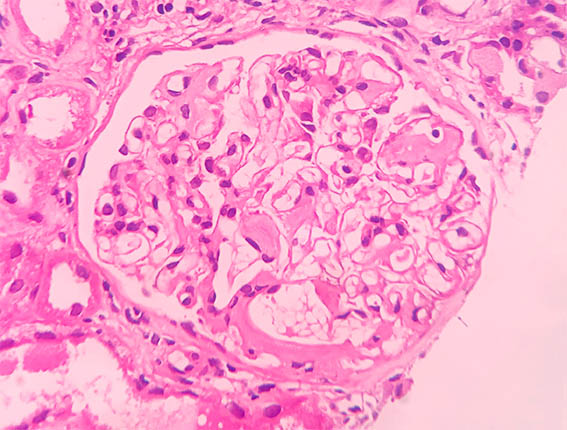

Figura 4. H&E, X400.